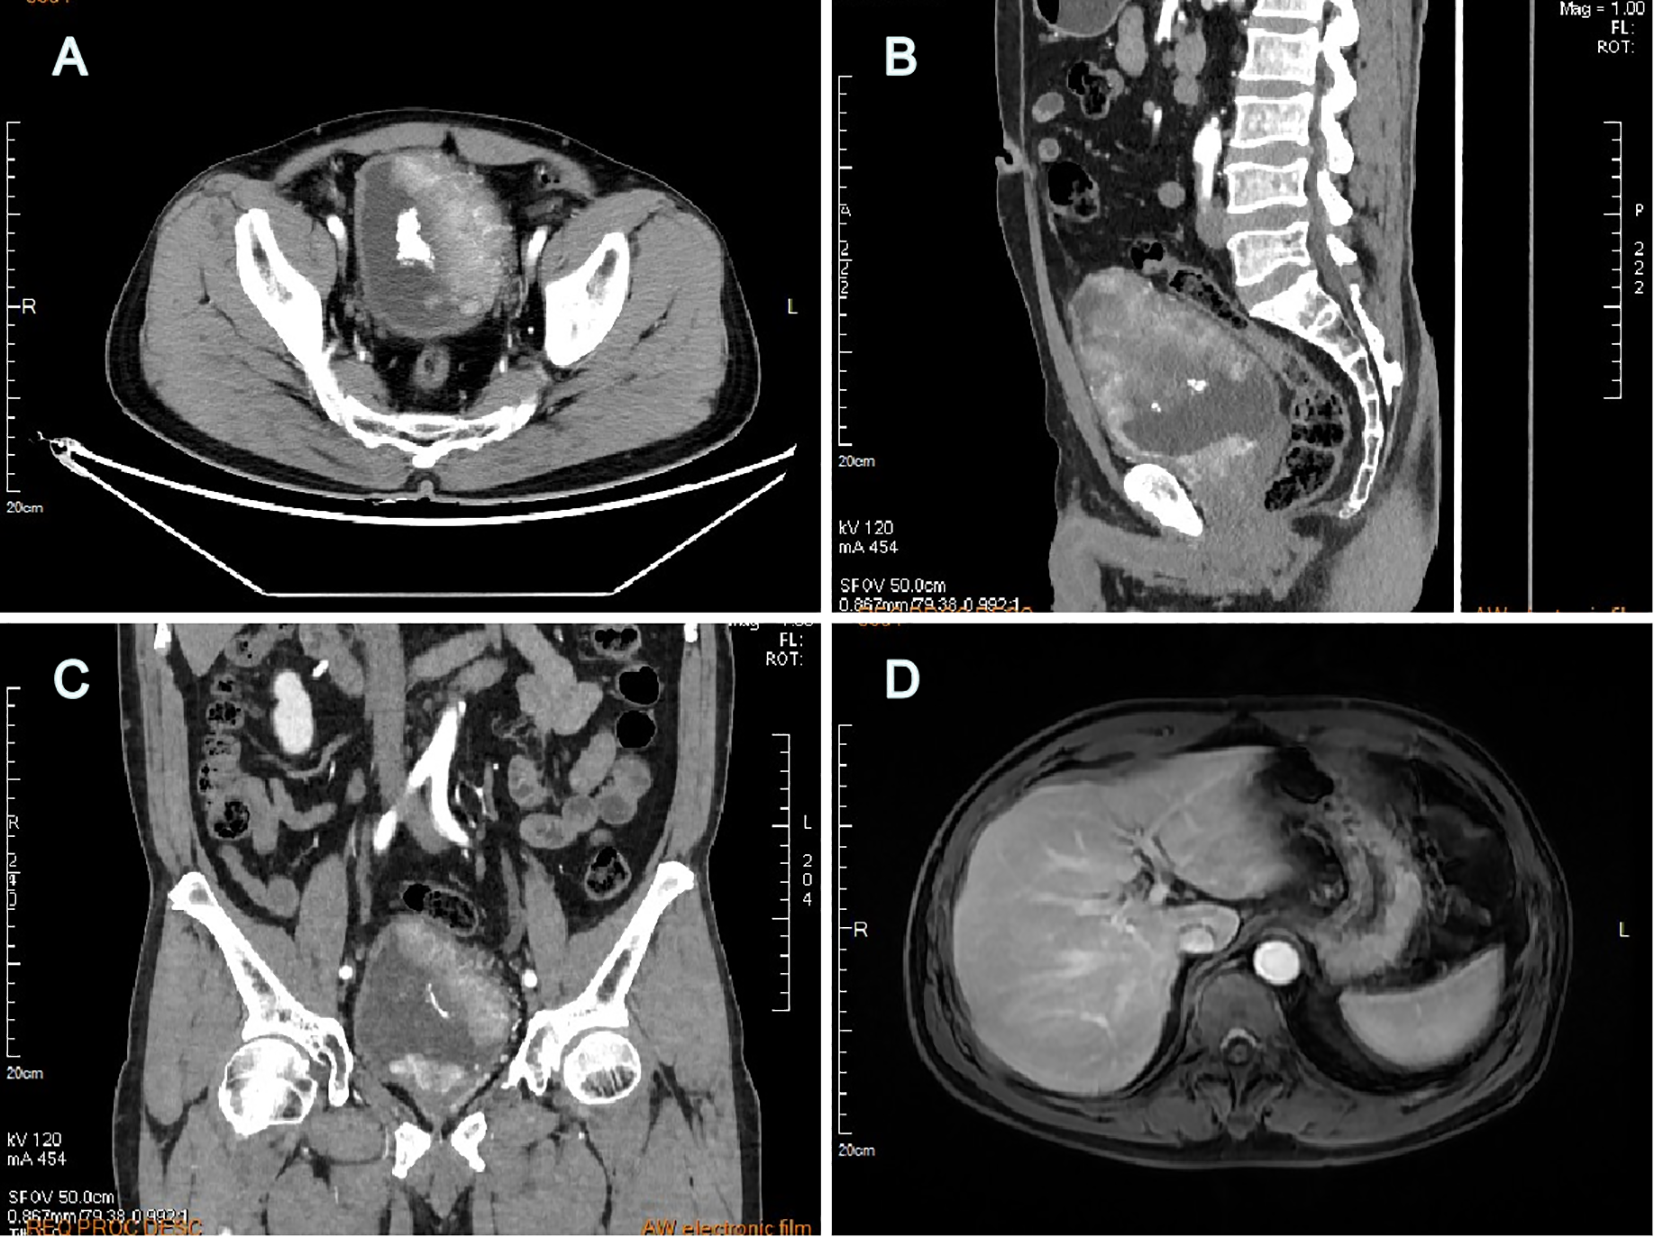

A 60-year-old man with intermittent gross hematuria and frequent urination for over 2 months was found to have multiple bladder-occupying lesions on ultrasonography at the local hospital and then presented to our hospital. Physical examination revealed a large hard immobile mass in the middle of the lower abdomen while his liver, gallbladder, spleen, kidneys, prostate, testis, and epididymis were unremarkable. Urinalysis showed a red blood cell (RBC) count of 995.35/ul, white blood cell (WBC) count of 26.05/ul, and protein of +1. Computed tomography urography (CTU) revealed irregular thickening of the bladder wall with multiple lesions, the largest measuring 97mm x 48mm, with unclear boundaries and calcifications on the surface. The lesions showed significant enhancement on contrast imaging, with extension into the prostatic urethra (Figures 1A–C). Hepatitis B surface antigen (HBsAg), hepatitis B e-antibody (HBeAb), and hepatitis B core antibody (HBcAb) were positive. Hepatitis B surface antibody (HBsAb), hepatitis B e-antigen (HBeAg), and hepatitis C virus antibody (HCV-Ab) were negative. The hepatitis B virus DNA (HBV-DNA) quantitative result was 1.75x105 IU/ml. Liver, renal, and coagulation function tests were all normal. Serum AFP was 2,329ng/ml and remained significantly elevated at 1,802ng/ml after anti-HBV treatment with tenofovir pofol fumarate for 1 week before surgery. PSA, CEA, CA125, CA153, and CA199 were all within normal limits. The AFP isoform L3 percentage was 34.8%, and the GALAD score, which determines risk of HCC based on patient sex, age, and serum levels of AFP, AFP-L3, and des-gamma-carboxy prothrombin (DCP), was ≥2.57. Ultrasound of the digestive system showed a fatty liver and a 24mm x 15mm hypoechoic area in the left lobe of the liver, suggesting uneven fat distribution. Liver transient elastography showed a Controlled Attenuation Parameter (CAP) value of 233dB/m and a stiffness E value of 4.3kPa, both within normal limits. Abdominal magnetic resonance imaging (MRI) with contrast revealed no significant abnormalities in the liver, gallbladder, pancreas, or spleen (Figure 1D). Scrotal ultrasound showed no abnormalities in the bilateral testis or epididymis. Chest CT showed no significant abnormalities in bilateral lungs.

Figure 1

Computed tomography urography revealed multiple large lesions of the bladder (A) transverse plane, (B) sagittal plane, (C) coronal plane; Abdominal MRI with contrast revealed no detectable liver lesions (D).